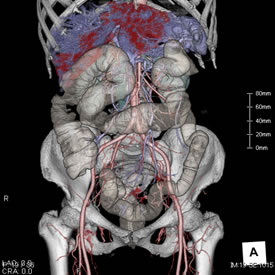

内臓動脈瘤への経皮的塞栓術

脾門部の動脈瘤に対して塞栓用コイルにて塞栓術を施行しています。